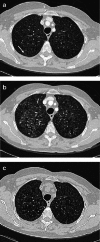

Objectives: Pulmonary Langerhans cell histiocytosis (PLCH) is a rare interstitial granulomatous disease that usually affects young adults who are smokers. Chest computed tomography (CT) allows a confident diagnosis of PLCH only in typical presentation, when nodules, cavitated nodules and cysts coexist and predominate in the upper and middle lungs.

Methods: This article includes a pictorial essay of typical and atypical presentations of PLCH at initial chest CT. Various appearances of PLCH are illustrated and possible differential diagnosis is discussed.

Results: PLCH can present with some aspecific features that may cause diagnosis of the initial disease to be overlooked or other pulmonary diseases to be suspected. In cases of nodule presentation alone, the main differential diagnosis should include lung metastasis, tuberculosis and other infections, sarcoidosis, silicosis and Wegener's disease. In cases of cysts alone, the most common diseases to be differentiated are centrilobular emphysema and lymphangiomyomatosis. Clinical symptoms are usually non-specific, although a history of cigarette smoking, coupled with the presence of typical or suggestive findings at imaging, is key to suspecting the disease. Atypical presentations require surgical biopsy for diagnosis.